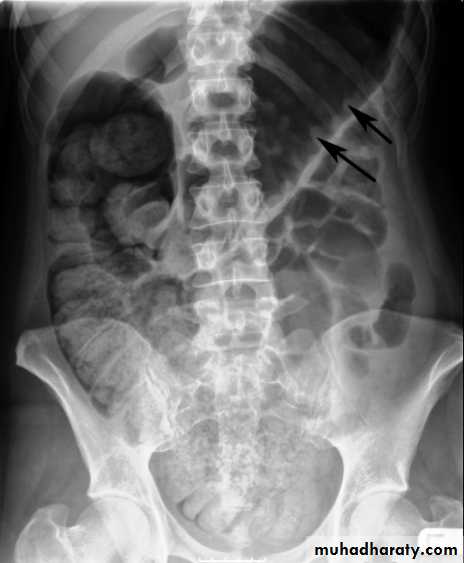

Small bowel obstruction

Large bowel obstruction

Valvulae conniventes

Present

Absent

Number of loops

Many

Few

Distribution of loops

Central

Peripheral

Haustra

Diameter

3 – 5 cm

More than 5 cm

Radius of curvature

Small

Large

Fecal material

Causes of bowel dilatation

• Mechanical SB obstruction : small bowel dilation with normal or reduced caliber of colon• Mechanical LB obstruction: dilated colon down to the point of obstruction. May be accompanied by small bowel dilation if the ileocecal valve becomes incompetent

• Generalized paralytic ileus: SB and LB dilatation, gas may be present in the rectum